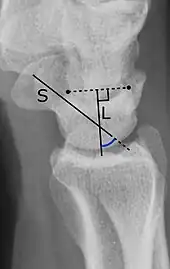

The SL angle is an indicator of dorsal intercalated segment instability deformity (DISI). The SL angle goes between:[1]

- A line through the long axis of the scaphoid bone.

- A line perpendicular to the distal articular surface of the lunate bone.

It should normally be 30°-60°.[1]